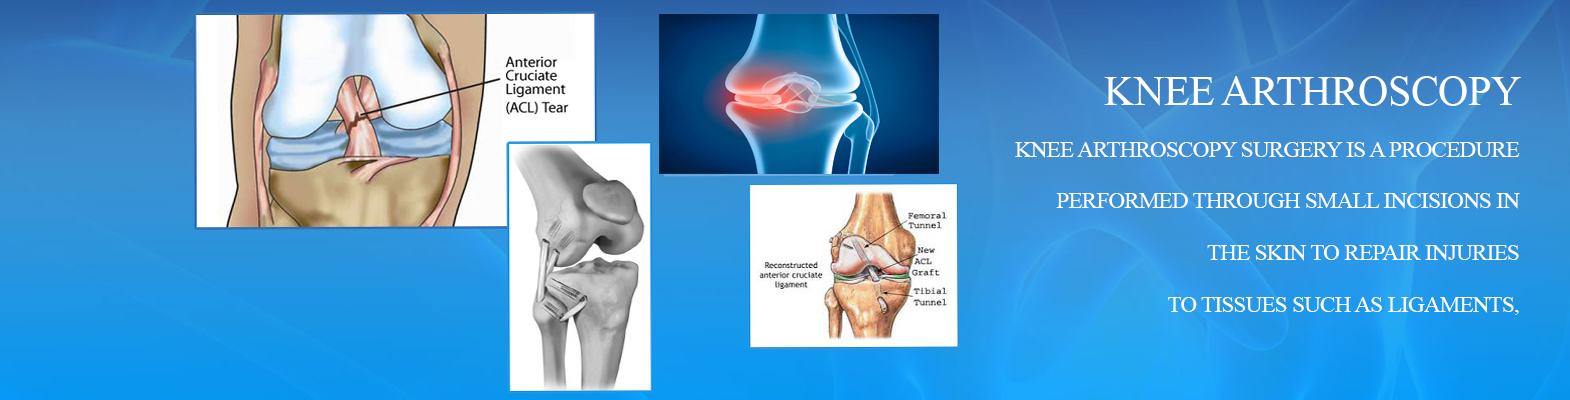

Knee Arthroscopy

A Knee Arthroscopy is a minimally invasive surgical (MIS) procedure, which provides a quick, easy and clear view of the inside of the knee through a pencil size slim, high-resolution camera known as an Arthroscope. Knee arthroscopy is also known by different names such as knee synovectomy, Meniscus repair or simply knee surgery. Our joint care center provide cost effective Knee Arthroscopy Surgery for Knee Pain Treatment in Jaipur, India.